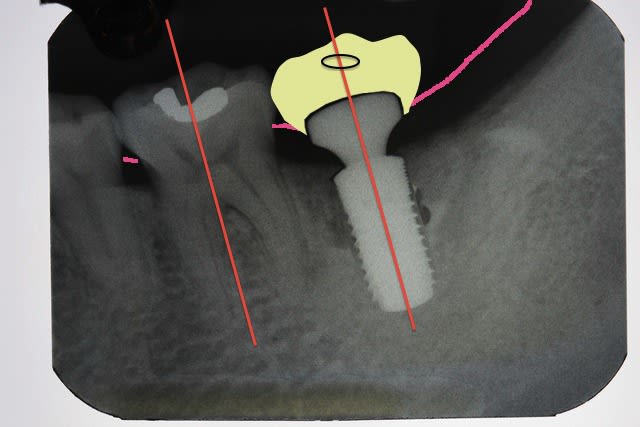

fric fric fric !

l'étude de cas et les guides chir au départ rendent l'implantologie peu rentable apparemment